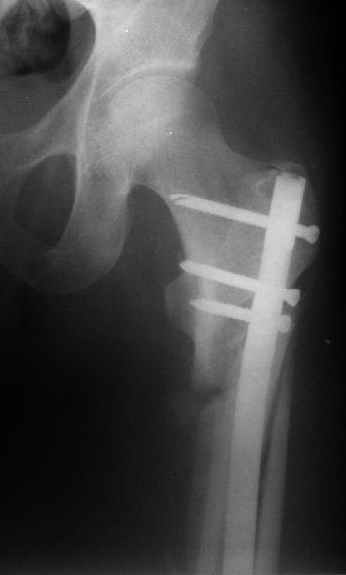

Картинка красивая, но на мой взгляд, не совсем оптимальная: Слишком медиально введён стержень - риск аваскулярного некроза головки бедра.

вариант межфрагментарного шинирования - зона достаточно простительная т.е. чрезвертельные переломы потенциально хорошо срастаются при любом

расположении сопредельных отломков- хорошая локальная васкуляризация. В приведённом случае я бы предпочёл принцип межфрагментарной компрессии (рекон/гамма нэйл 130- 135) принципу шинирования перелома.

Поясни, пожалуйста, почему решил шинировать косой чрезвертельный перелом?

Женя, эта картинка показывает не оптимальное лечение вертельных переломов в моем представлении, а особенности дизайна упомяутого фиксатора.

В частности, его возможности при фиксации переломов проксимального отдела бедра - в сравнении с другими, имеюшими лишь по одному статическому и динамическому отверстию и с кондуктором для введения 2 винтов.

Это было года 2,5 назад, мы тогда еще уточняли возможности шинирования с угловой стабильностью гвоздем с поперечным расположением винтов при переломах проксимального отдела бедра. Пациенту не пришлось приобретать намного более дорогой рекон или проксимальный гвоздь. В приложении еще несколько примеров применения того гвоздя при высоких переломах бедра, в том числе с более латеральной точкой входа. Гвоздь изгибаем для этого.